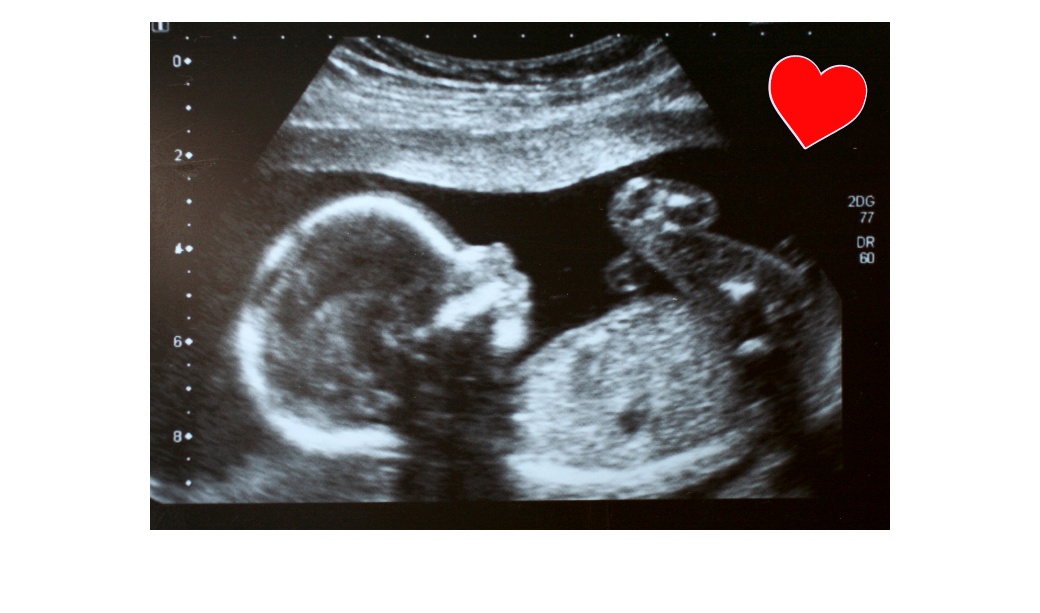

Никога не си твърде млад, за да бъдеш интернет звезда и това неродено бебе го доказва. Майка му Джен Кардинал публикувала клип в YouTube, който възхитил милион потребители.

Към видеото майката написала: „На нашия 14-седмичен ултразвук бебето ни пляскаше, така че аз изпях песен с нашия лекар, докато съпругът ми снимаше.“

Видеото показва как бебето пляска седем пъти, докато Кардинал и нейният лекар могат да бъдат чути да пеят извън кадър „If You’re Happy and You Know It“. Ритъмът не е нещо, с което повечето бебета се раждат. Но това – което тепърва ще се ражда – май го има в изобилие.

Родителите могат да бъдат чути да се забавляват развълнувално на заден план, докато лекарят след това превърта лентата назад, за да изглежда, че бебето пляска заедно с тяхното пеене.

Някои коментатори побързали да нарекат видеото фалшиво, но майката разказва пред TODAY, че макар нейният лекар да манипулирал кадрите, за да удължи аплодисментите, първите три пляскания наистина били „много истински“.

„Ходихме на ултразвук. Бебето ни плесна два-три пъти. Бяхме изумени, смяхме се“, казва тя. Тогава лекарят предложил: „Хайде да изпеем една песен“. "Той върна кадъра и го пусна отново, докато пеем, така че изглежда, че бебето пляска. Много забавно.“

Говорител на Американския колеж по акушество и гинекология казва пред TODAY.com, че е правдоподобно бебето да е пляскало поне веднъж, обяснявайки:

„Ембрионите правят всякакви безсмислени движения в утробата, без да знаят, че го правят – но ако пляскащото движение е истинско, случило се е само веднъж и вероятно са го редактирали, за да се повтаря.“